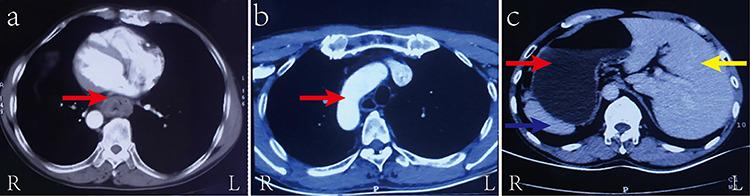

Situs inversus totalis (SIT) is a rare congenital condition, which is characterized by abnormal placement of the thoracic and abdominal organs. The incidence of this condition is estimated to be from 1/8000 to 1/25,000. There have been minimal reports on SIT patients with esophageal cancer. In this report, we discuss a patient with SIT complicated by middle and lower esophageal cancer who underwent laparoscopic and thoracoscopic esophagectomy with intrathoracic anastomosis, and provide useful information with regards to treatment of this rare condition.

全内脏转位是一种罕见的先天性疾病,其特征是胸腹部器官位置异常。据估计,这种疾病的发病率为1/8000至1/25000。关于全内脏转位合并食管癌患者的报道极少。在本报告中,我们讨论了一名全内脏转位合并食管中下段癌的患者,该患者接受了腹腔镜和胸腔镜食管切除术并进行了胸内吻合,并提供了有关这种罕见疾病治疗的有用信息。